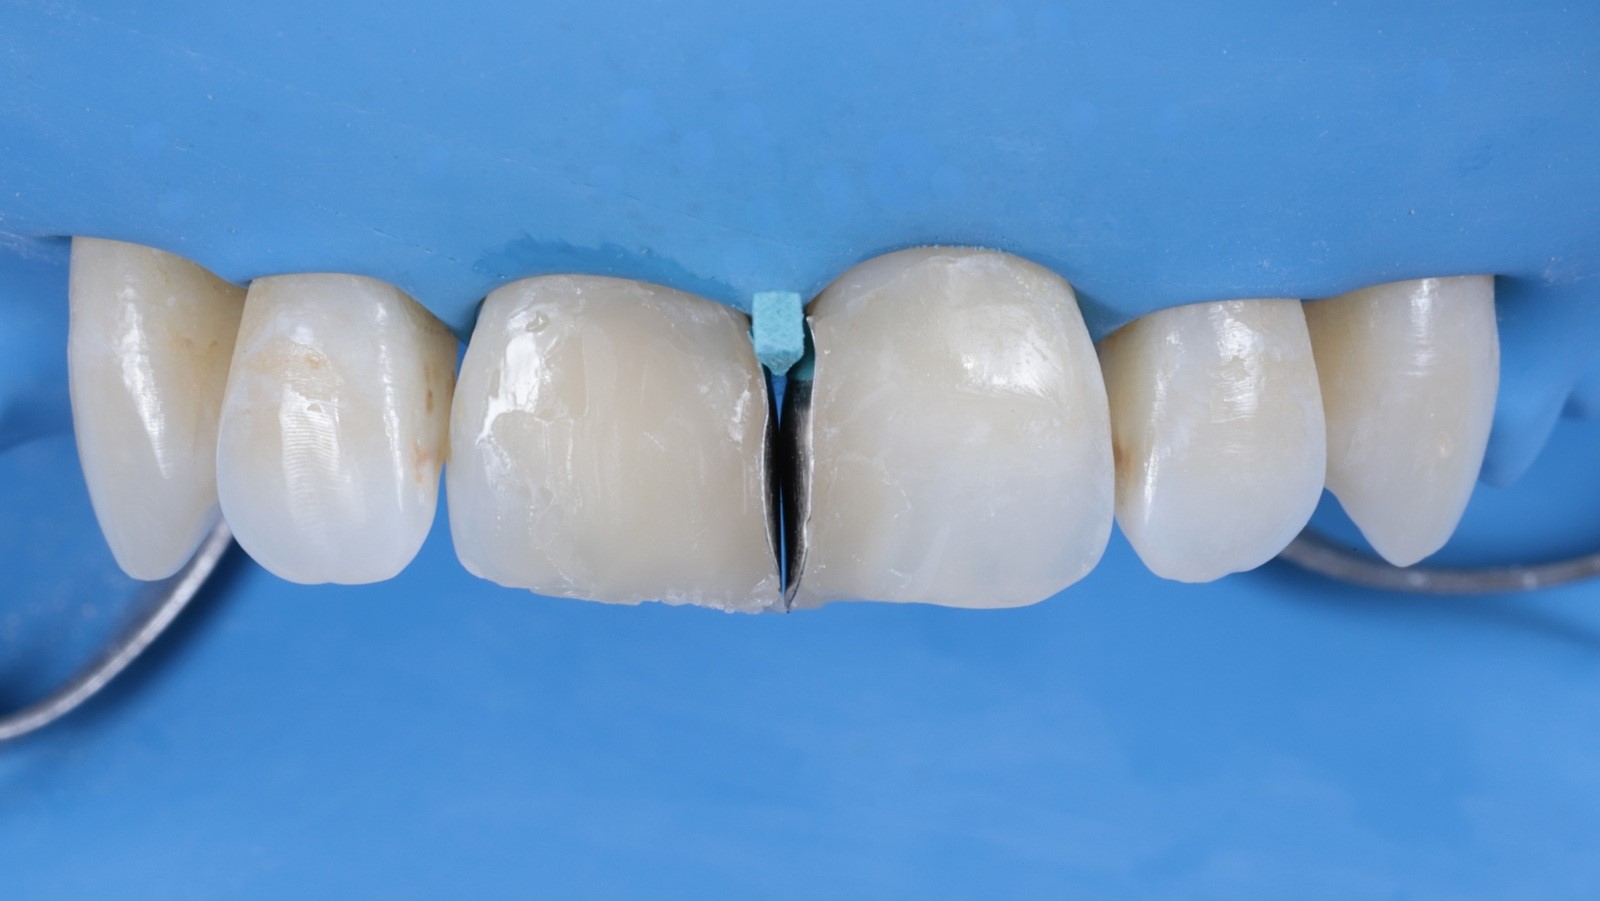

The surgical field was isolated to provide a clean and dry working environment.

The old composite and any decayed tissue was carefully removed to prepare the teeth for the new restoration.

The teeth were etched with 35% orthophosphoric acid and bonded using iBOND Universal (Kulzer).